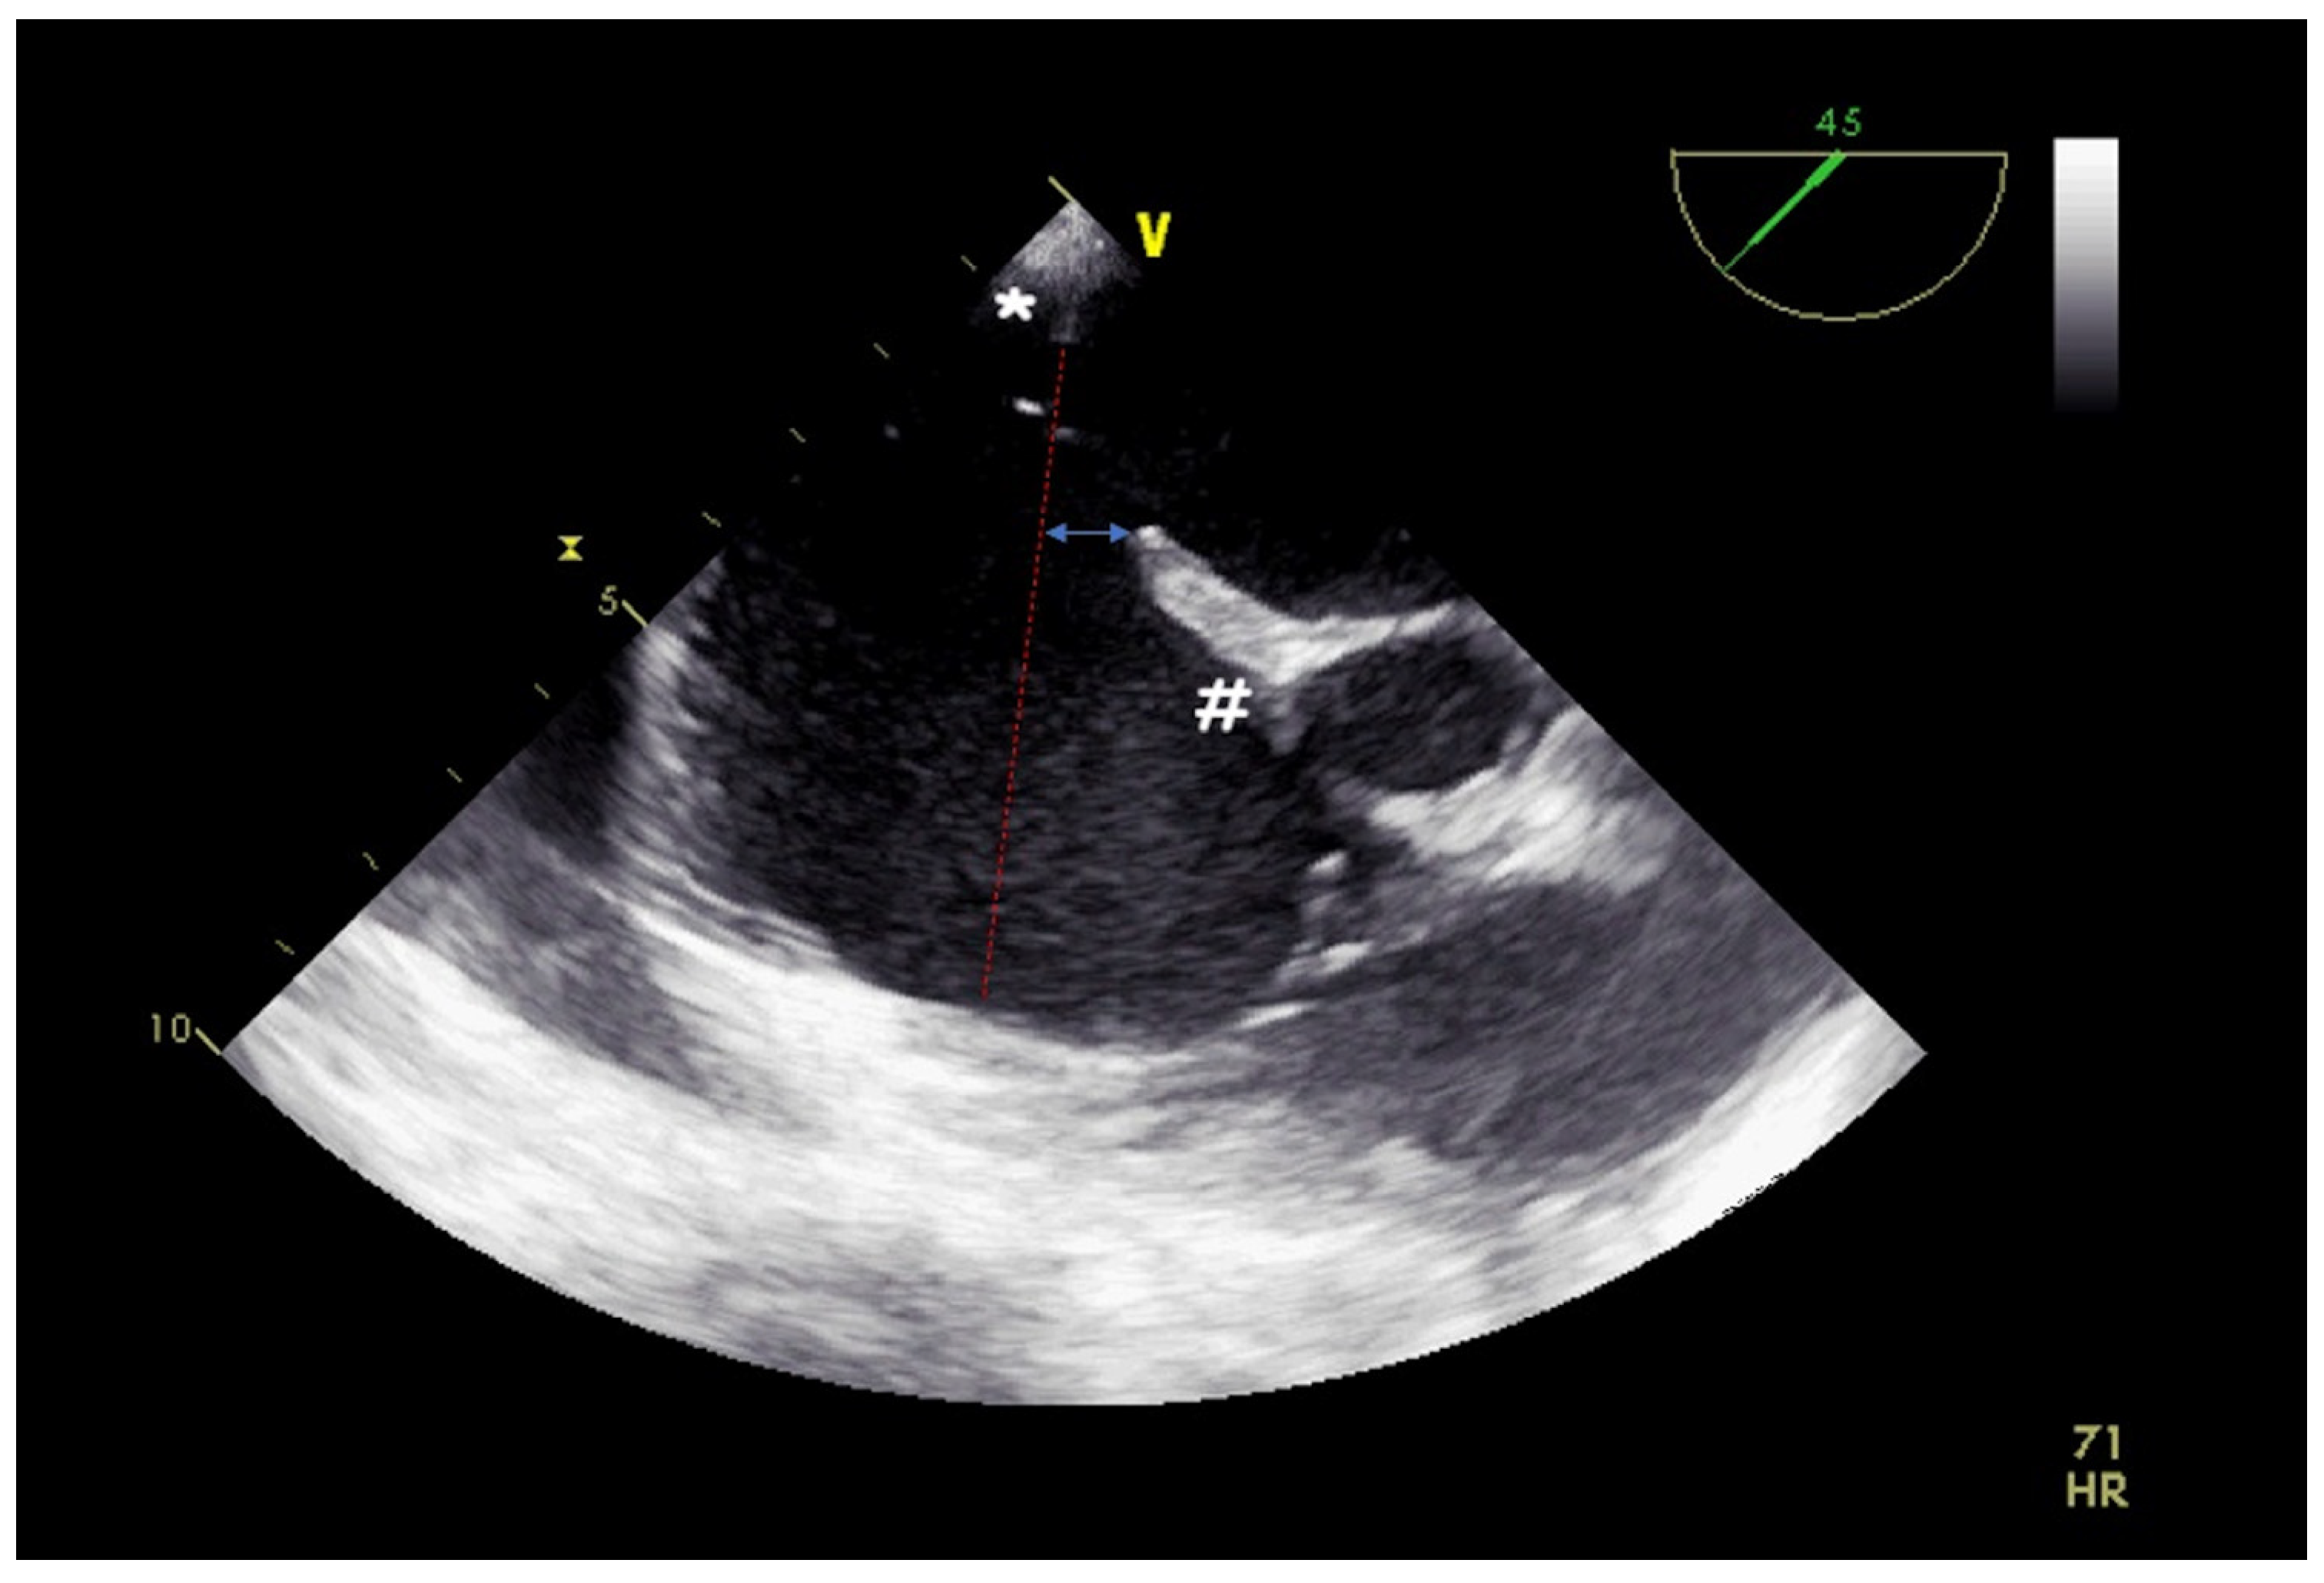

4. Leak Closure of Atrial Switch Operation Baffles